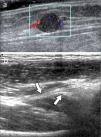

En operadores entrenados (8) permite una buena evaluación de los tendones del manguito rotador, incluso comparable con la RM (9) en busca de tendinosis, tendinopatía cálcica y roturas (figuras 2-4).

En el tendón de la porción larga del biceps es útil para estudio de tenosinovitis o luxación. En articulación acromioclavicular podemos encontrar compromiso degenerativo o inflamatorio, derrame, quistes periarticulares o signos indirectos de disyunción. Se visualiza el receso articular glenohumeral posterior en búsqueda de derrame y también los planos musculares periarticulares. La bursitis subacromiodeltoidea se manifiesta como engrosamiento y/o líquido en la bursa (figura 5). La evaluación dinámica permite observar fenómenos de pinzamiento por el ligamento coracoacromial y también pinzamiento subacromial a la bursa o los tendones.